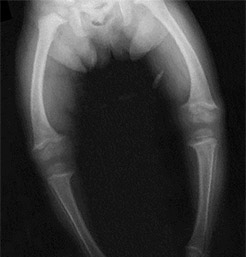

Рахит рентген

Рахит рентген 136 фото